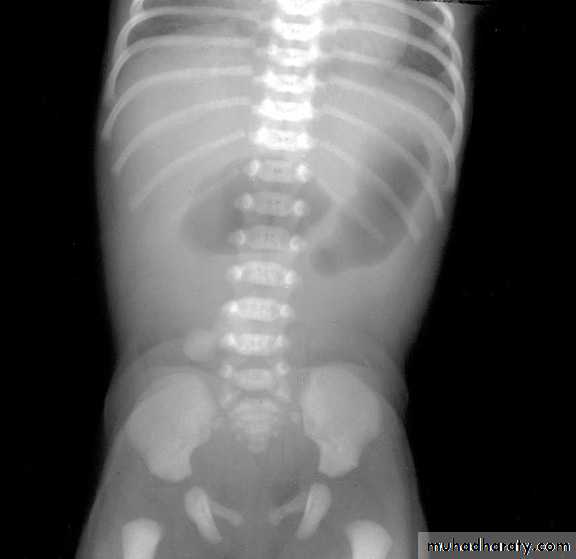

A 2 week old boy presents with history of constipation, abdominal distension and bilious vomiting. The pictures show the operative findings and radiographic investigation done for him.1. What is the diagnosis?2. What is the underlying pathology for this condition?3.Describe the findings in all slides.4. What other investigations used to reach the diagnosis?5. What are the steps of management for this condition?